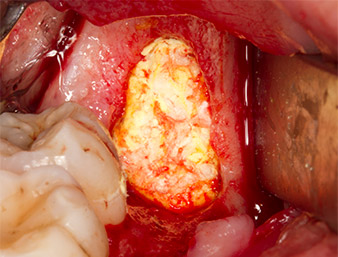

Le tissu recouvrant le reste radiculaire n’est pas entièrement ossifié et est essentiellement constitué de tissu de granulation modifié par l'inflammation (Fig. 4).

Pour obtenir un matériau autogène en vue du traitement ultérieur de la plaie, des fragments osseux sains sont collectés autour du reste radiculaire à l'aide d’un insert piézochirurgical (Piezomed B5) (Fig. 5).